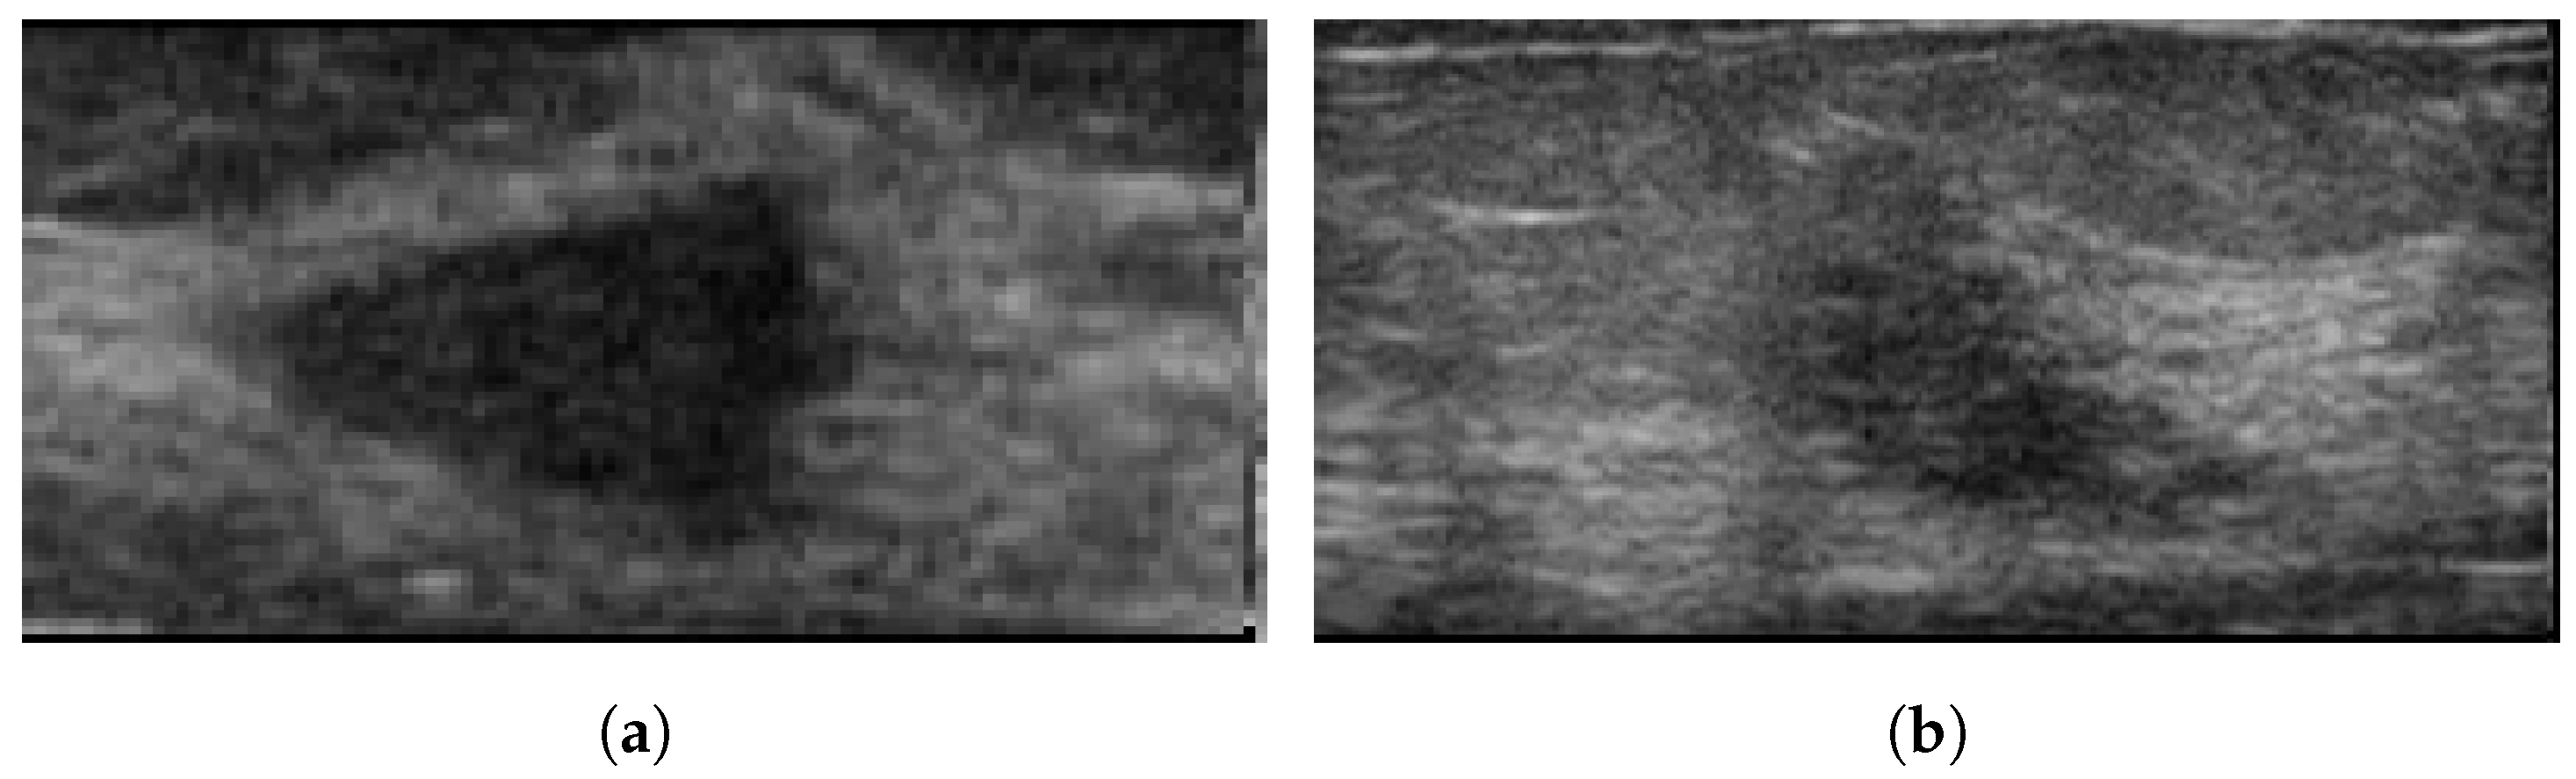

4.3. Ultrasonography

- Han, S.; Kang, H.K.; Jeong, J.Y.; Park, M.H.; Kim, W.; Bang, W.C.; Seong, Y.K. A deep learning framework for supporting the classification of breast lesions in ultrasound images. Phys. Med. Biol. 2017, 62, 7714. [Google Scholar] [CrossRef]

- Jabeen, K.; Khan, M.A.; Alhaisoni, M.; Tariq, U.; Zhang, Y.D.; Hamza, A.; Mickus, A.; Damaševičius, R. Breast Cancer Classification from Ultrasound Images Using Probability-Based Optimal Deep Learning Feature Fusion. Sensors 2022, 22, 807. [Google Scholar] [CrossRef]

- Tanaka, H.; Chiu, S.W.; Watanabe, T.; Kaoku, S.; Yamaguchi, T. Computer-aided diagnosis system for breast ultrasound images using deep learning. Phys. Med. Biol. 2019, 64, 235013. [Google Scholar] [CrossRef]

- Hijab, A.; Rushdi, M.A.; Gomaa, M.M.; Eldeib, A. Breast Cancer Classification in Ultrasound Images using Transfer Learning. In Proceedings of the 2019 Fifth International Conference on Advances in Biomedical Engineering (ICABME), Tripoli, Lebanon, 17–19 October 2019; pp. 1–4. [Google Scholar]

- Kim, J.; Kim, H.J.; Kim, C.; Lee, J.H.; Kim, K.W.; Park, Y.M.; Kim, H.W.; Ki, S.Y.; Kim, Y.M.; Kim, W.H. Weakly-supervised deep learning for ultrasound diagnosis of breast cancer. Sci. Rep. 2021, 11, 24382. [Google Scholar] [CrossRef] [PubMed]